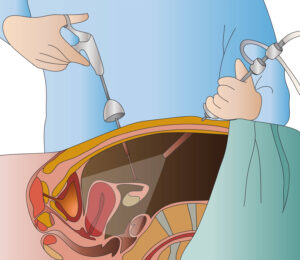

Λαπαροσκόπηση

Η λαπαροσκόπηση από γυναικολόγο είναι μια χειρουργική διαδικασία που χρησιμοποιεί τη λαπαροσκοπία για να εξετάσει ή να επέμβει σε προβλήματα που σχετίζονται με τον γυναικολογικό συνδυασμό, όπως οι όγκοι, οι κύστεις, οι εκδηλώσεις της εσωτερικής επιφάνειας της μήτρας (ενδομητρίωση), η εξασθένηση του κολπικού δακτυλίου, και άλλα προβλήματα.

Η διαδικασία πραγματοποιείται με τη χρήση ενός λαπαροσκοπίου, που είναι ένα εργαλείο που περιλαμβάνει μια φωτοκύτταρο και μια κάμερα, και εισάγεται μέσα στον κοιλιακό χώρο μέσω μιας μικρής τομής. Ο γυναικολόγος παρακολουθεί την εσωτερική επιφάνεια του κοιλιακού χώρου σε πραγματικό χρόνο σε μια οθόνη.

Οι πλεονεκτήματα της λαπαροσκοπίας συγκεκριμένα για γυναικολογικές επεμβάσεις περιλαμβάνουν:

- Ελάχιστος Επεμβατικός Χαρακτήρας: Οι τομές που απαιτούνται για τη λαπαροσκοπία είναι συνήθως πολύ μικρές σε σύγκριση με τις παραδοσιακές χειρουργικές επεμβάσεις.

- Σύντομος Χρόνος Ανάρρωσης: Οι γυναίκες που υποβάλλονται σε λαπαροσκοπία συνήθως έχουν σύντομους χρόνους ανάρρωσης σε σύγκριση με παραδοσιακές χειρουργικές επεμβάσεις.

- Λιγότερος Πόνος: Επειδή οι τομές είναι μικρές, ο πόνος μετά τη λαπαροσκοπία μπορεί να είναι λιγότερος σε σύγκριση με άλλες μεθόδους.

Οι γυναικολόγοι χρησιμοποιούν τη λαπαροσκοπία για ποικίλες επεμβάσεις, συμπεριλαμβανομένων της αφαίρεσης όγκων, της διόρθωσης της ενδομητρίωσης, της αφαίρεσης των όνεων, και άλλων επεμβάσεων που απαιτούν προσπέλαση στον γυναικολογικό χώρο.